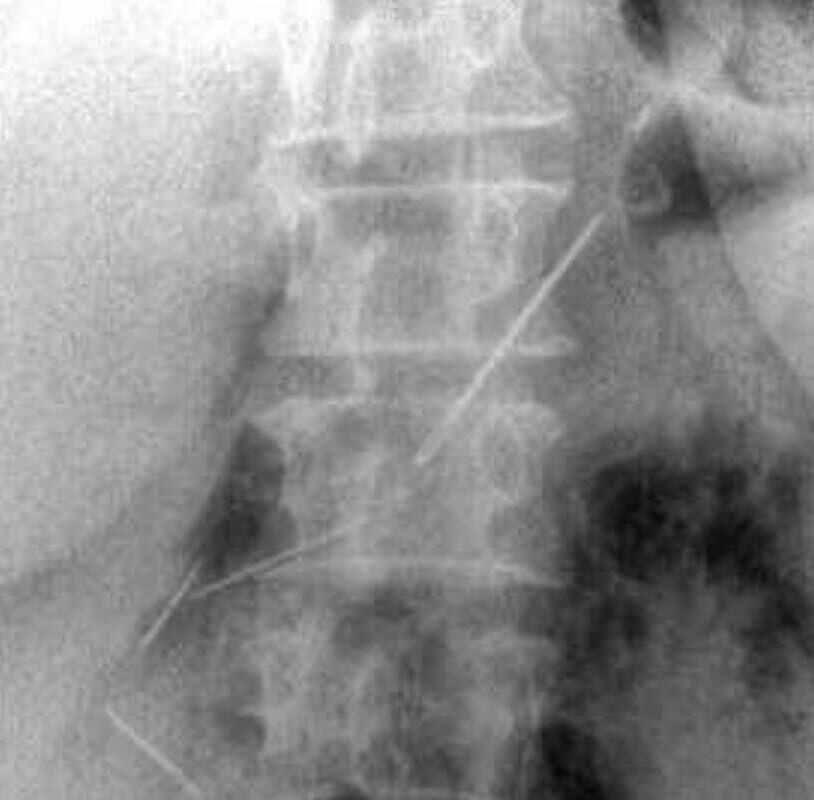

Пожилая женщина обратилась в Красногорскую больницу с жалобами на боли в животе. Пациентку обследовали и выяснили, что у нее в брюшной полости и одной передней брюшной стенке находятся четыре иглы.

Выяснилось, что женщина проглотила их около месяца назад — при каких обстоятельствах это случилось, не уточняется. За время нахождения в организме иглы успели обрасти тканями.

Медики провели пациентке лапаротомию и удалили все инородные предметы. Одна из игл проникла в поджелудочную железу, но орган все же удалось сохранить. Вмешательство прошло успешно.